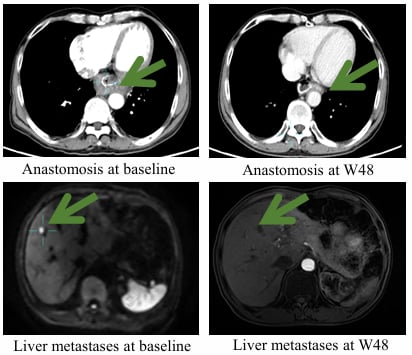

尤其值得一提的是,其中1例经多线治疗的转移性胃癌患者,此前疾病已进展(PD,累及肝脏并伴吻合口复发),在接受IMC002 CAR-T疗法治疗后,成功逆转了疾病进展,获得了完全缓解(CR)。更令人惊喜的是,该患者的无瘤生存状态已持续超过60周(即一年多),这为晚期患者带来了真正的“治愈”希望。这充分证明了IMC002在清除肿瘤细胞方面的强大潜力。

图1. 该患者IMC002治疗前(左图)与治疗后(右图)对比图